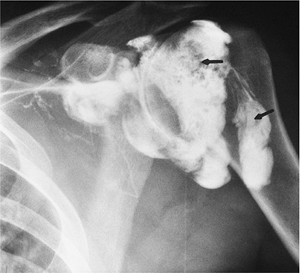

FIGURE 7-24 AP radiograph of an arthrogram demonstrating a recurrent tear with contrast in the subdeltoid bursa (arrows). Note the resected clavicle (large arrow).